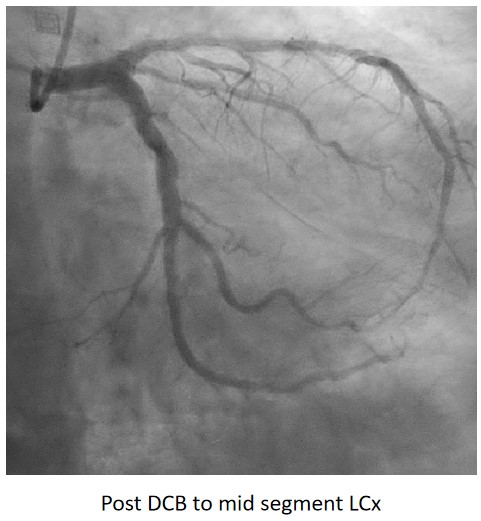

Urgent coronary angiography showed smooth LMCA with severe 3-vessel involvement. There was diffuse LAD lesion with critical stenosis at proximal-to-mid segment. Mid-segment of LCx was 90% stenosed while RCA was heavily calcified with critical stenosis at its mid segment. Our strategy will be complete revascularisation by employing DCB-only strategy.

Complete revascularisation was achieved with 2-staged procedures. Up-front plaque modification with rotational atherectomy/IVL with IVUS was planned but limited by patient¡¯s cost constraint. Vascular access obtained with transradial puncture with 6 Fr sheath. Guiding catheter (GC) Judkins Right 4.0 (Cordis, USA) 6 Fr was used to engage right coronary ostium. Runthrough Floppy (Terumo, Japan) wire was wired down RCA. Pre-dilatation balloons were unable to cross the heavily calcified mRCA lesion. Next, GC was changed to Amplatz Left 1.0 (Cordis, USA) for better support and proceeded for further lesion preparation with cutting balloon Wolverine (Boston Scientific, USA) 3.5 x 10 mm and DCB Prevail (Medtronic, USA) 3.0 x 20 mm was deployed. We scheduled him for staged PCI to the left coronaries in 2 weeks time via transradial approach with 6 Fr sheath. GC XB LAD 3.5 (Cordis, USA) 6 Fr was used to engage left coronary ostium. Runthrough Floppy was wired down LCx. Mid-distal LCx was prepared with Pantera Pro (Biotronik, Germany) 2.5 x 15 mm and DCB Pantera Lux (Biotronik ,Germany) 3.0 x 15 mm was deployed. Finally, we wired down LAD with Runthrough Floppy. Mid-distal LAD lesion was prepared with Pantera Pro 2.5 x 15 mm and DCB Pantera Lux 3.0 x 30 mm was deployed. Proximal LAD lesion, which was calcified, was further prepared with Wolverine 2.5 x 10 mm before DCB Pantera Lux 3.5 x 30 mm was deployed. Final post-PCI results were acceptable, achieving complete revascularisation for him.